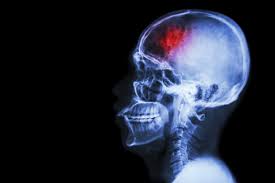

Traumatic brain injury

Traumatic brain injury (TBI) is a complex injury with a broad spectrum of symptoms and disabilities. The impact on a person and his or her family can be devastating. The purpose of this site is to educate and empower caregivers and survivors of traumatic brain injuries. This site aims to ease the transition from shock and despair at the time of a brain injury to coping and problem solving. Bookmark this site for the latest medical breakthroughs and brain research, the highest quality treatment for brain damage, the symptoms of brain injuries and the nation's best traumatic brain injury rehabilitation centers and resource information.